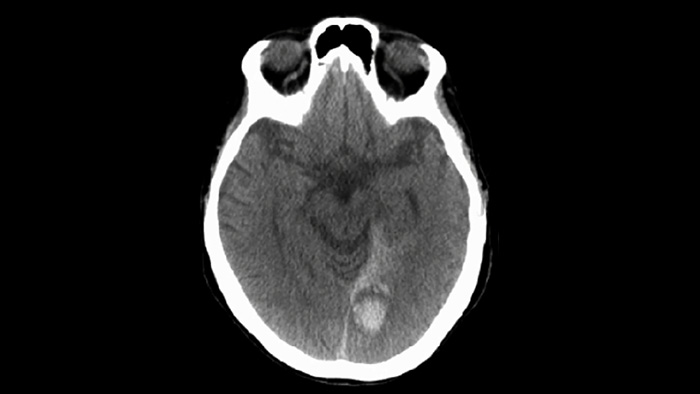

Compruebe si hay sangrados alrededor del procedimiento

THC (similar a la TC)

Use las imágenes de SmartCT Soft Tissue de la suite Neurovascular para comprobar el éxito del tratamiento e identificar hemorragias.